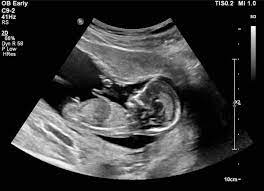

ارسال تصاویر پزشکی از دستگاههای سونو گرافی به سامانه پکس

با توجه به پی گیری مدیریت آی تی دانشگاه علوم پزشکی اراک و درخواست های گروه رادیولوژی کلیه دستگاههای سونو گرافی در استان در بیمارستانهای تابعه در حال حاضر به سامانه پکس مرتبط می باشد و امکان ارسال تصاویر و ذخیره در سامانه پکس وجود دارد که لینک تصاویر آن جهت بیماران پیامک می گردد . این فرآیند در راستای کاهش هزینه ها و بی نیاز بودن از خرید کاغذ مخصوص سونوگرافی می باشد.